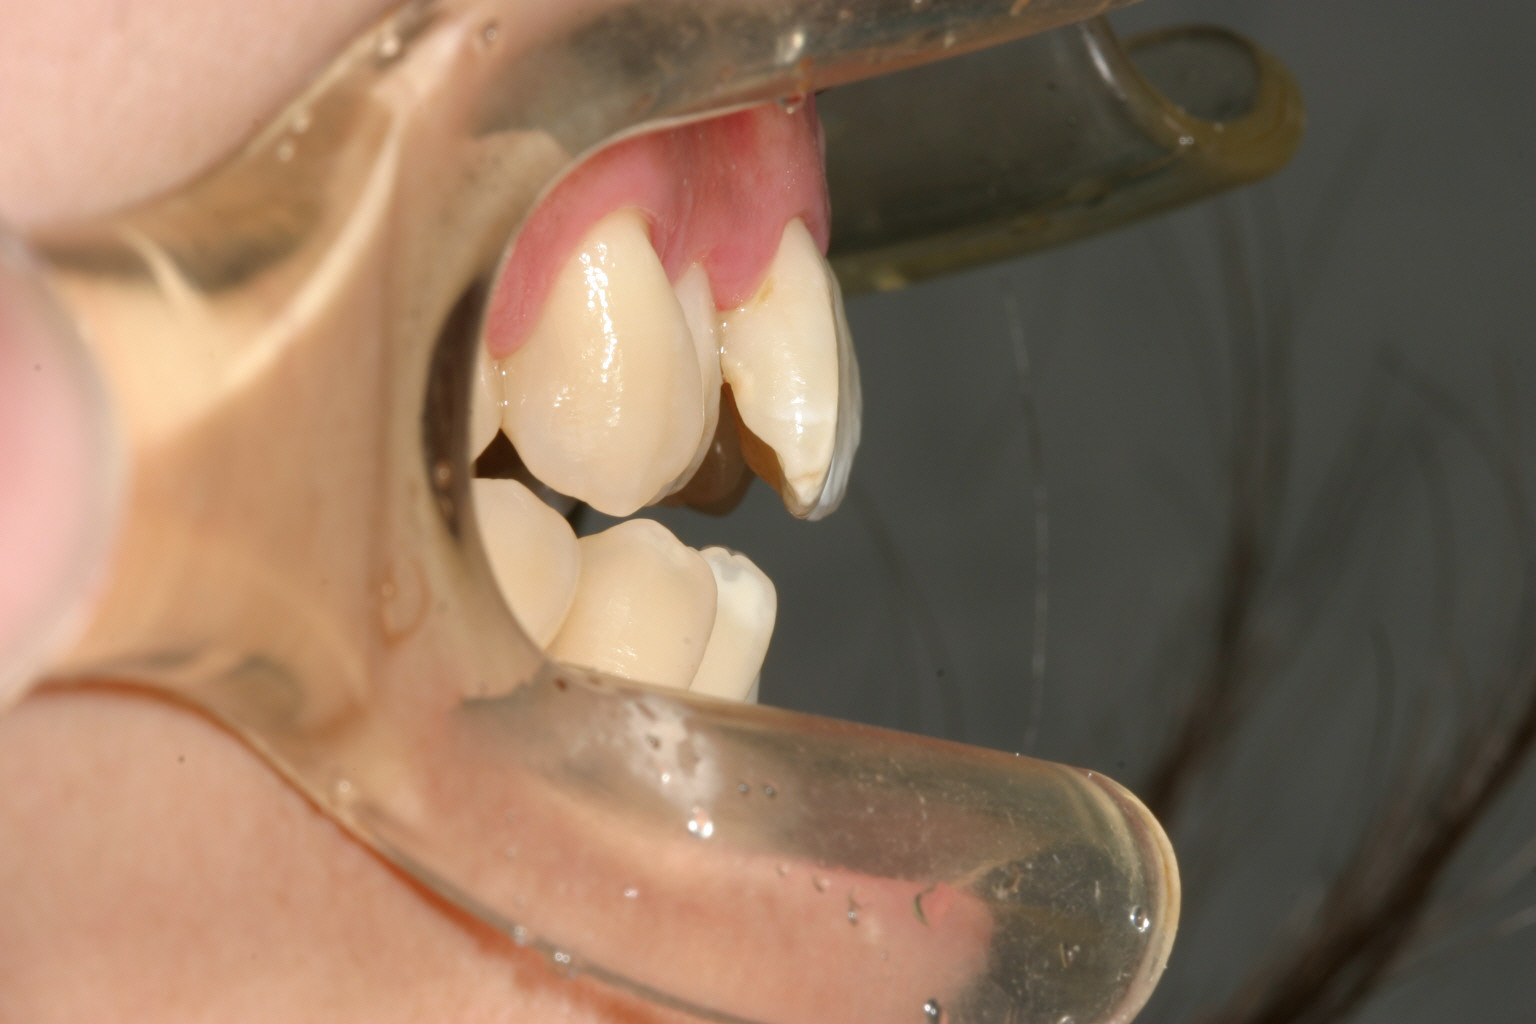

開咬は殆ど閉じてきています。

側面観も抜群です。